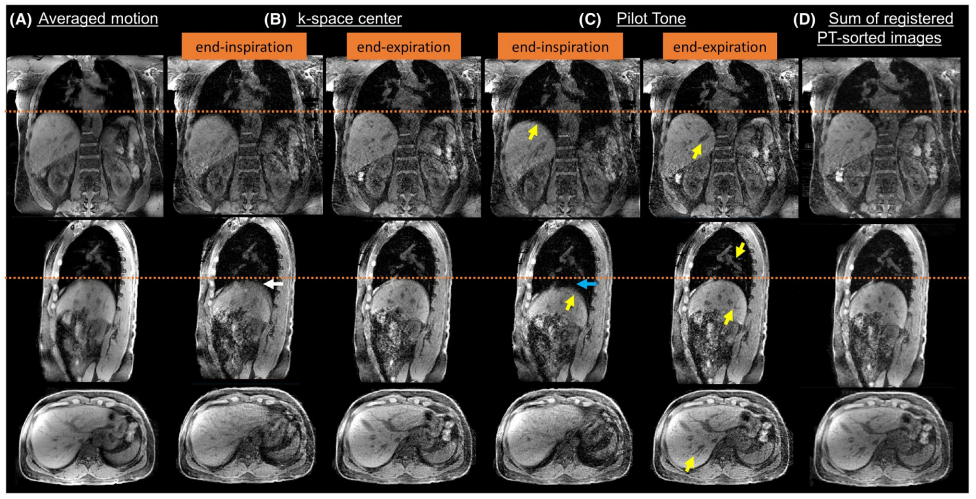

4. Free-Breathing Hybrid Technique for Simultaneous.png

Keerthivasan M, Bruno M, Solomon E, Brown R, Brantner D, Block K, Chandarana H

Investigative Radiology, 2025